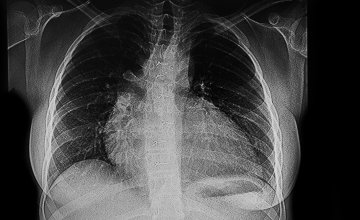

Uvećano srce (kardiomegalija): Zašto se javlja kod žena, djece i starijih osoba?